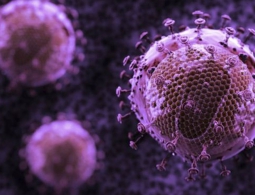

Российские ученые синтезировали молекулу, предотвращающую заражение ВИЧ

Поиском лекарств от опасных заболеваний занимаются многие специалисты по всему миру. Но болезнь, как известно, проще предотвратить, чем лечить. И недавно отечественные ученые из Федерального научно-клинического центра физико-химической медицины синтезировали особые молекулы нуклеиновых кислот, предо...